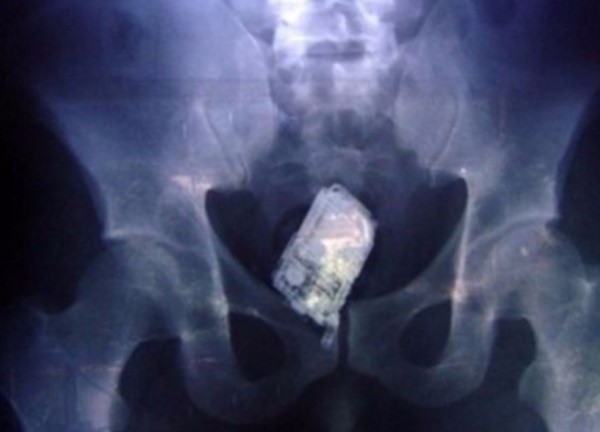

보고에 따르면 실제 적지 않은 성인이 항문에 이물질을 집어 넣었다가 빠지지않는 사고를 당한다거 하는데요.

항문 주위에 신경이 많아 큰 자극을 받을 수 있기 때문이라고 합니다.